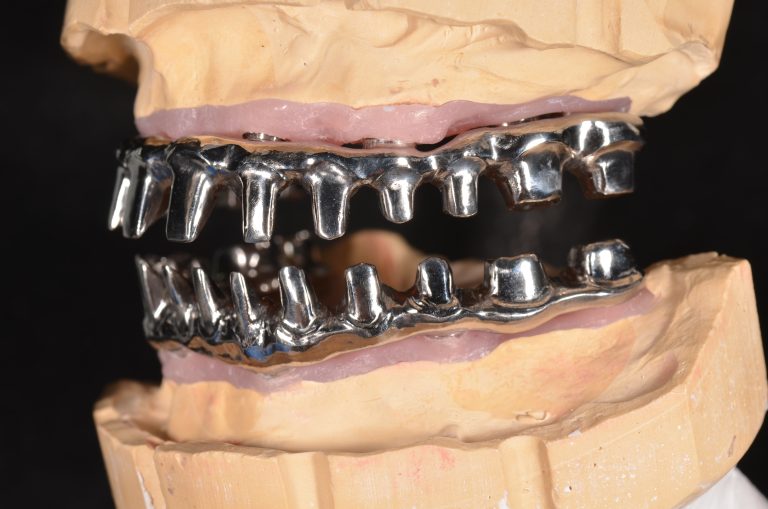

- 鈦金屬支架 + 單顆全鋯牙冠:內層鈦金屬一體成型支架,咬合咀嚼聲較小,硬度強。因為是單顆獨立全鋯冠,維修方便。表面光亮不易染色,全鋯表面光滑易清潔,較不會有異味,外觀可以長期保持在良好的狀態。

| 優點 | 塑鋼假牙有些許彈性,咬合初期較易適應。重量較輕 | 美觀,不易磨損。陶瓷表面光滑易清潔 | 最美觀,不易磨損。陶瓷表面光滑易清潔,維修最簡單,只需更換損壞的單顆假牙 |

| 缺點 | 需定期更換,塑膠感重,需要最多咬合空間。易染色,維修可能需整副假牙送回技工所處理 | 重量最重,因全鋯表面堅硬,咬合初期需要訓練適應。維修可能需整副假牙送回技工所處理 | 重量稍重,因全鋯表面堅硬,咬合初期需要訓練適應 |

以下為鈦金屬支架+單顆全鋯牙冠實際案例。